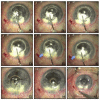

Methods: In this narrative review, the procedure of DALK is described in detail. Important pre, intra, and postoperative considerations are discussed with illustrative examples for better understanding. A comprehensive literature review was conducted in PubMed/Medline from January 1995 to July 2017 to identify original studies in English language regarding DALK. The primary endpoint of this review was the narrative description of surgical steps for DALK, its pitfalls, and management of common intraoperative complications.

Results: A standard DALK procedure can be successfully performed taking into consideration factors such as age, ophthalmic co-morbidities, status of the crystalline lens, retina, and intraocular pressure. Careful trephination and dissection of the host cornea employing appropriate technique (such as big bubble technique, manual dissection, visco-dissection, etc.) suitable for the specific case is important to achieve good postoperative outcomes. Prompt identification of intraoperative complications such as double bubble, micro and macroperforations, etc. are vital to change the management strategies.